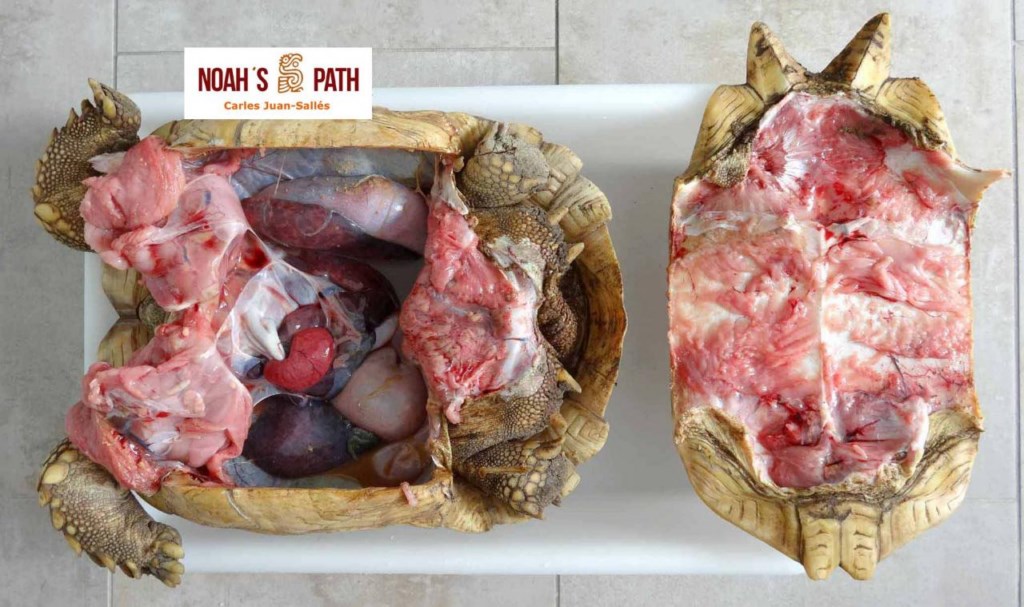

El examen post mortem ofrece una oportunidad única de acceso a todos los tejidos del paciente para diagnóstico de las causas de enfermedad y muerte, y por lo tanto es esencial para medicina preventiva y curativa en grupos de animales, seguimiento de casos, estudios sobre enfermedades, control de zoonosis, medicina de la conservación, y patología forense. En Noah's Path pensamos que un examen post mortem de este tipo de fauna debería ser realizado siempre que sea posible por patólogas/os especializadas/os con el fin de obtener el máximo de información y obtener las muestras más adecuadas.